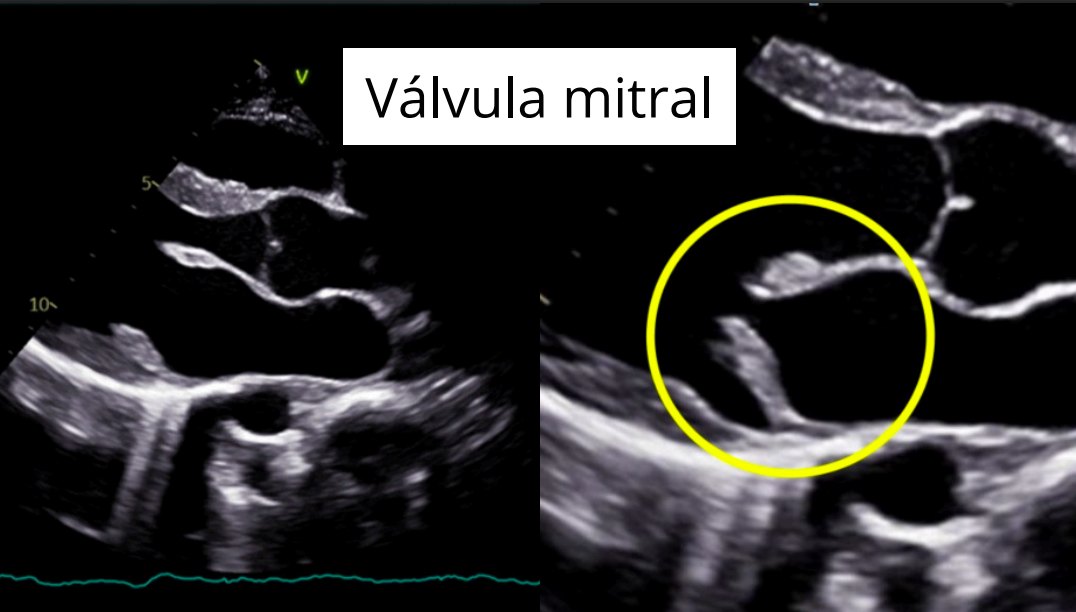

Enfermedad valvular mixomatosa mitral

- Degenerativa y progresiva.

- Afecta la válvula mitral, que se engrosa y deforma por acumulación de material mixomatoso.

- Provoca regurgitación mitral, con flujo retrógrado hacia la aurícula izquierda durante la sístole.

Hallazgos ecocardiográficos

- Regurgitación mitral (Doppler color).

- Engrosamiento y prolapso valvular.

- Dilatación de AI y VI.

Regurgitación mitral:

Engrosamiento de las valvulas